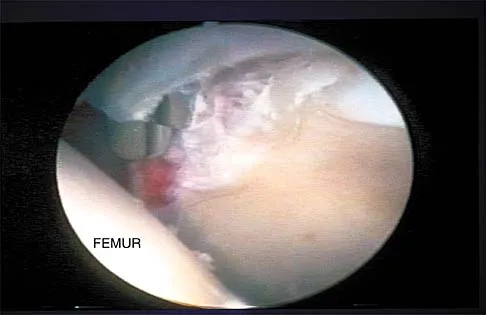

A patient undergoes hip arthroscopy, and the pathology is seen in Figure 18. What is the most likely diagnosis?

Explanation